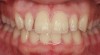

Figure 4  Teeth with multiple surface and structural defects required improving the smile design following orthodontics.

Figure 4

Figure 5   Final composite restorations of the four maxillary incisors.

Figure 5

Case 2 demonstrates composite restoration following orthodontics. Surface concavities on the facial of the lateral and central incisors, papillae loss between the central incisors, severe incisal wear on left central incisor, and a poorly shaped right lateral incisor were restored with composite. Placement of a clear matrix that reflected the gingiva allowing subgingival bonding and composite placement closed the gingival embrasure between the central incisors (Figure 4 and Figure 5).